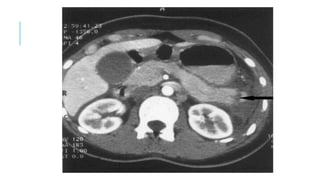

RETROPERITONEAL HEMATOMAS

Zone I – Mandatory Exploration

retroperitoneal hematoma

any zone requires exploration for

all penetrating injuries

Zone II retroperitoneal

hematomas resulting from blunt

trauma

Zone III explored only if

penetrating injury. Blunt trauma

usually causes venous bleeding

which requires fixation.